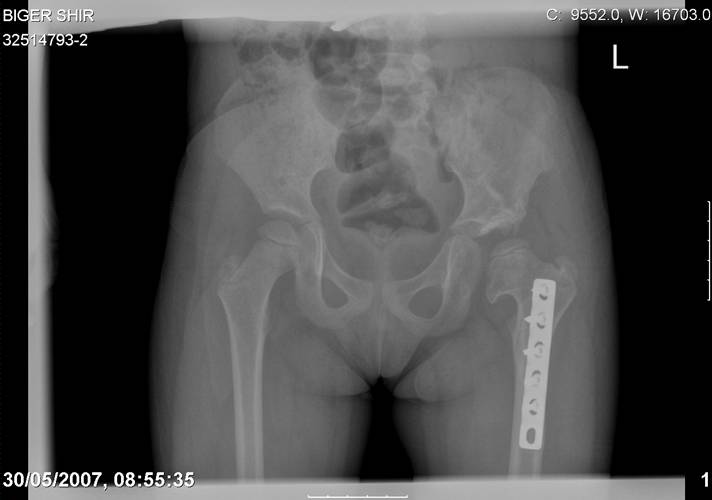

Chto by ne byt goloslovnym posilau vam svoi sluchai gde sdelal vse chto napisal vyshe